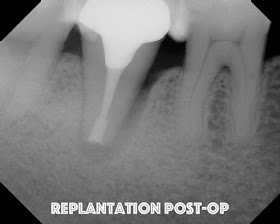

The tooth is replanted into the socket within 10 minutes of extraction. Firm pressure is placed for an extended period of time. No splinting

A seven year recall finds tooth #31 asymptomatic and fully functional. While the mesial bone looks irregular, there is no periodontal pocket. If you look at the initial photo of the extracted tooth, you can see the periodontal ligament, but there appears to be an area where the ligament had been lost. There was not visible fracture on that area of the root at that time. My assumption is that the pdl may not have ever reformed in that area - causing the current radiographic appearance.